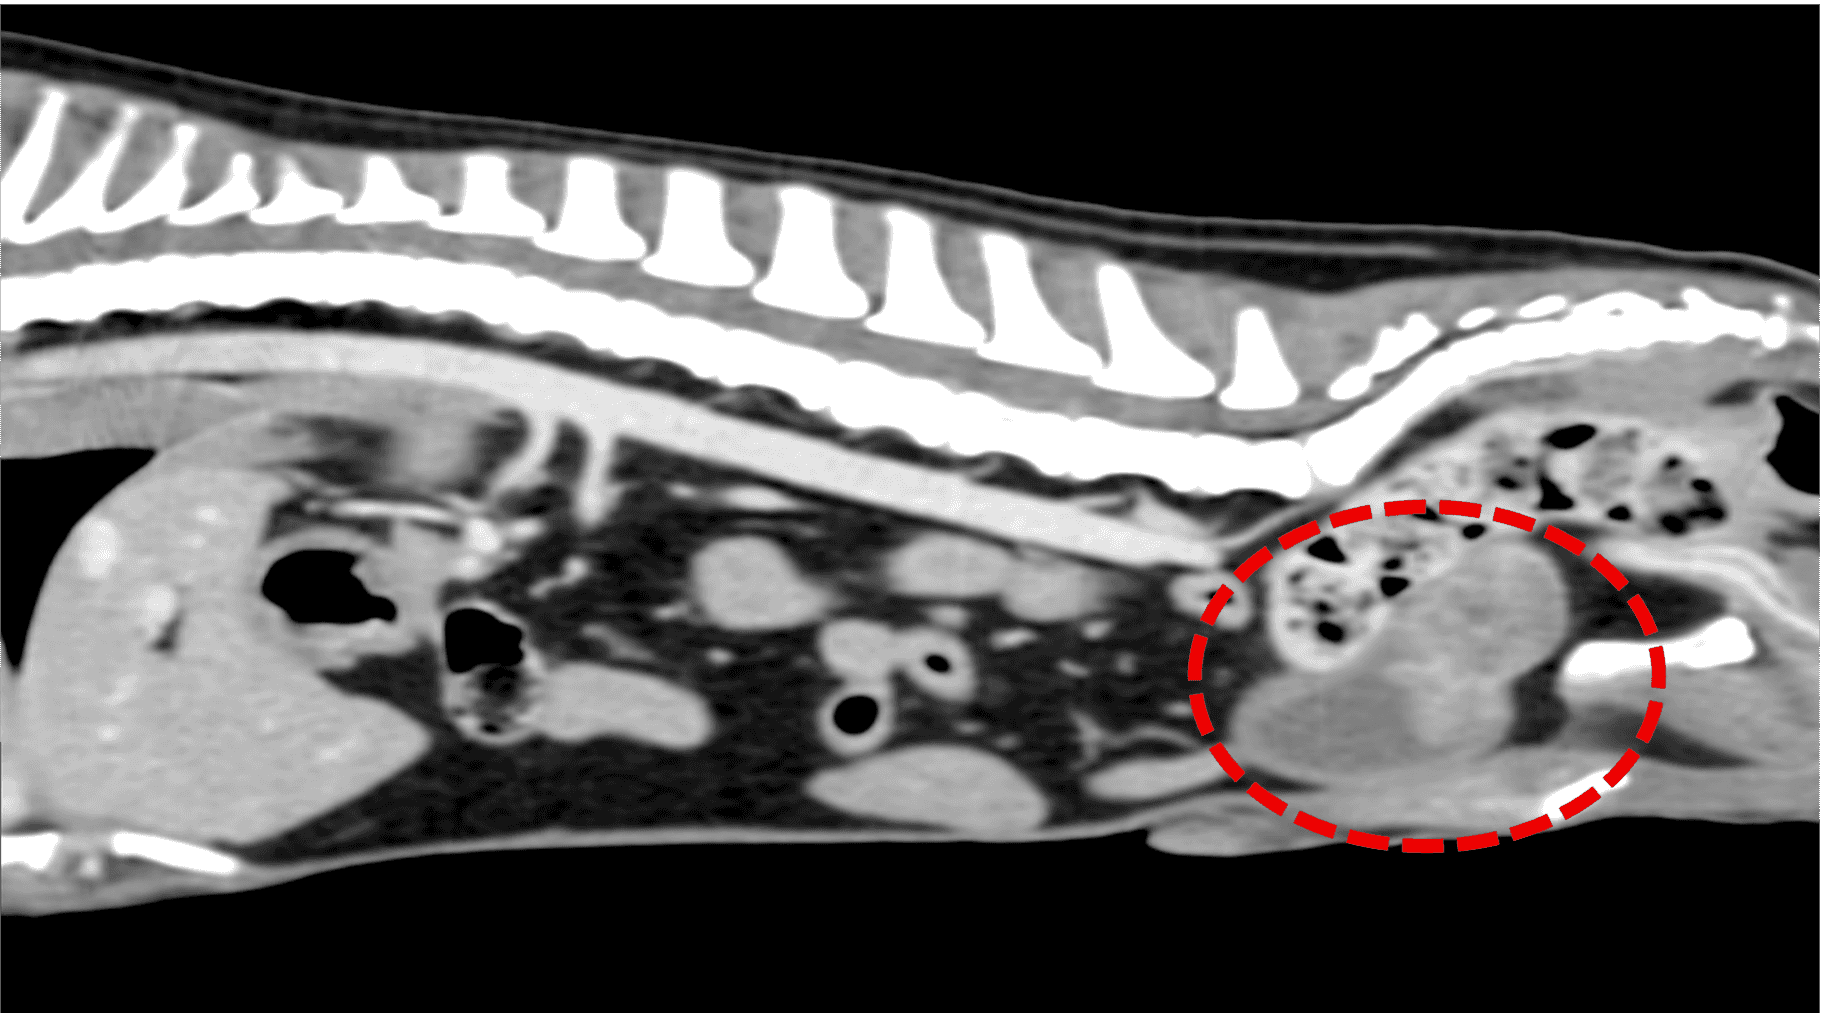

前立腺原発 尿路上皮癌うたがい →外力カテーテル法により得られた尿沈渣をBRAF遺伝子変異検査に外注 →BRAF遺伝子変異陽性 第14病日 CT撮影実施 (図2) →リンパ節、肺、その他臓器への転移所見なし

第24病日手術を実施した。胸骨剣状突起から恥骨前縁までの腹部正中切開を行い膀胱、前立腺へアプローチした。左右の尿管を確保し、膀胱移行部を露出後膀胱の近位で左右尿管を離断した。その後尿管にカテーテルを挿入し保持した。膀胱と前立腺、近位尿道を周囲脂肪組織から剥離し、前後膀胱動脈、前立腺動脈を処理し、最後に前立腺から十分距離を確保して尿道を骨盤腔内で結紮離断した。その後、左右尿管を腹壁に造瘻した孔を貫通させ、包皮外側の皮膚に縫合した。(図3,4)術後は左右尿管移設部位にカテーテルを留置し、入院管理を行った。入院5日目にカテーテルを抜去し、尿管移設部位からの尿排出を確認した後に退院となった。病理検査結果は、尿路上皮癌(移行上皮癌)完全切除であった。術後14日目に抜糸を行い、同日ラパチニブを開始した。またNSAIDsとしてフィロコキシブを併用した。 経過は良好であり、ラパチニブ開始から6ヵ月後に再発や転移が認められなかったことから、ラパチニブとフィロコキシブを中止し、現在術後約1年が経過するが再発や転移は認められていない。